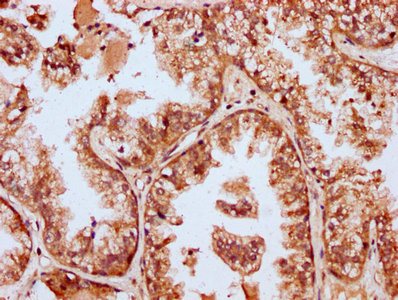

• IHC image of CSB-PA868322LA01HU diluted at 1:400 and staining in paraffin-embedded human prostate cancer performed on a Leica BondTM system. After dewaxing and hydration, antigen retrieval was mediated by high pressure in a citrate buffer (pH 6.0). Section was blocked with 10% normal goat serum 30min at RT. Then primary antibody (1% BSA) was incubated at 4°C overnight. The primary is detected by a biotinylated secondary antibody and visualized using an HRP conjugated SP system.